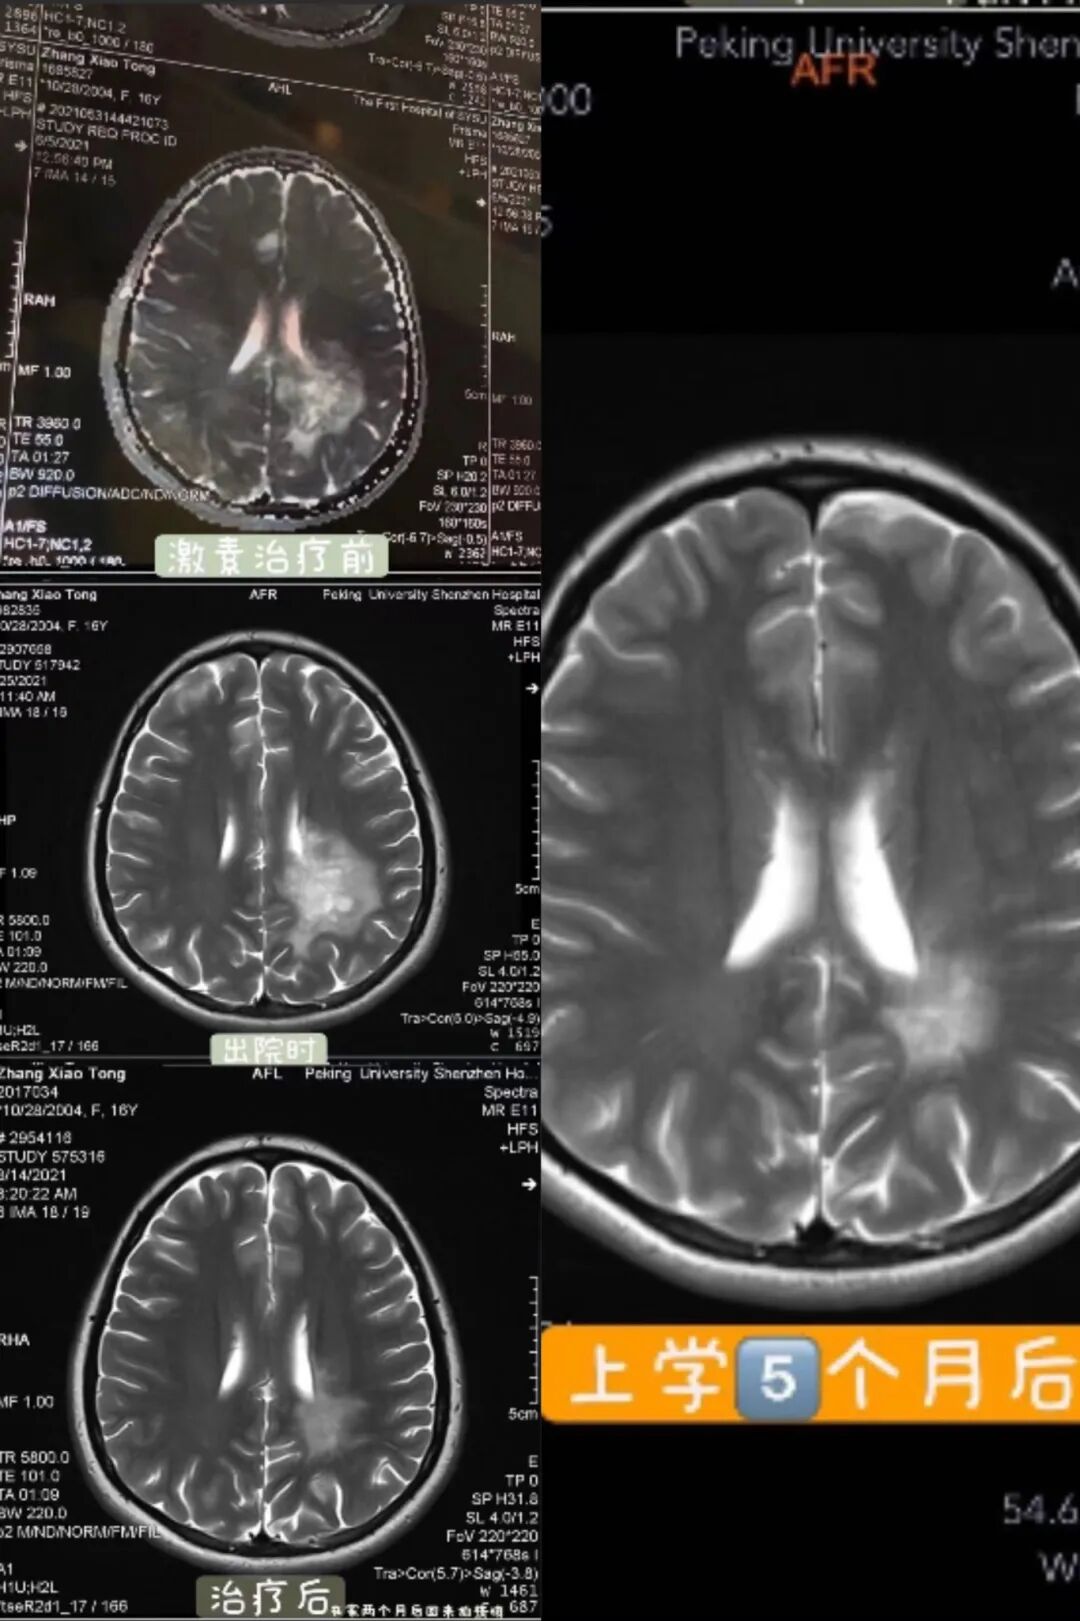

想着即使要做开颅手术,也得去更好的医院,于是我们换到更权威的医院去。医生一看我,就说:怪病啊,再照个核磁吧。这次的结果,不是胶质瘤,而是与之很容易混淆的免疫系统疾病脱髓鞘假瘤。对我来说,这又是一个陌生的名词,不过,总比恶性肿瘤要好。

住院一个月,我做了激素冲击治疗。大量的激素使我掉发、长胖、胃消化功能变差,高三一整年我都戴着口罩。直到现在,我仍然担心病症复发,小心翼翼地维护着我的健康。

章小桶 19岁

图 | 治疗过后的核磁图变化